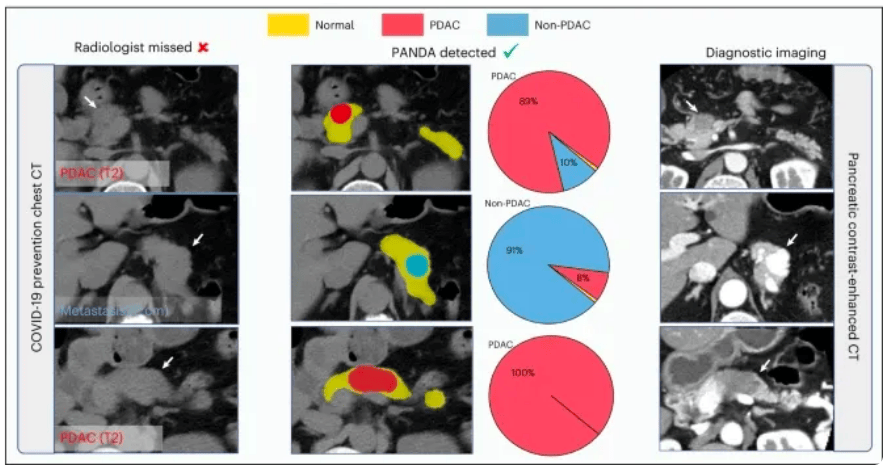

在前面提到的阿里所使用的PANDA模型中,最重要的一個技術,就是一種叫做**“圖像配準”**的技術,將對比增強CT上的病變標註“複製”到非對比CT圖像上。

用直觀的語言來描述,這種做法就是:先找兩張CT圖片,其中一張是普通CT,另一張是增強CT,之後,PANDA通過將兩張CT“重疊”在一起的辦法,來將增強CT上的病變區域準確地映射到普通CT的相應位置上。

需要説明的是,這裏的“重疊”,並不是簡單地將兩張圖片進行物理上的重疊,而是通過算法,識別兩張圖片中的特徵,並計算出它們之間的對應關係。

如此一來,AI就能結合增強CT高精準度,以及普通CT低成本,便於大規模普及的雙重優勢,在篩查癌症時,能夠又廉價又準確。

具體來説,在第一階段,PANDA會使用nnU-Net模型——一種特定的深度學習架構,精確地識別和分割出胰腺的區域。就相當於用畫筆勾勒出胰腺的輪廓。

在第二階段,一旦胰腺區域被定位和分割出來,PANDA的聯合分割和分類網絡,就會判斷這些區域是異常的還是正常的,如果異常,就要找出相應的病變區域。

第三階段(Stage 3)- 病變亞型分類:在檢測到病變之後,這個階段的目標是對這些病變進行更細緻的分類,比如區分不同類型的腫瘤或病變。